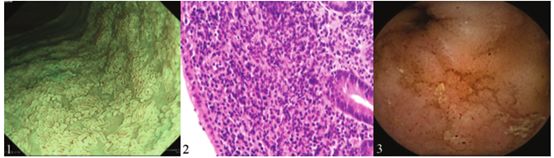

一名24岁女子因持续腹痛、水样腹泻及呕吐三个月而入院。实验室检测显示轻度炎症,c反应蛋白水平为0.72 mg/dL,白细胞计数为7290/mm3。粪便培养未检出致病菌。计算机断层扫描显示小肠黏膜增厚和大量腹水。内镜示大肠黏膜正常,除回肠末端的一些区域,其中窄带成像证明了绒毛消失(图1)。组织学检查示固有层淋巴细胞浸润严重,但未见明确血管炎(图2,H&E,×200)。胶囊内窥镜显示上空肠和盆腔回肠有广泛的瘀点,绒毛消失(图3)。入院1个月后,患者出现蝴蝶疹和关节炎。实验室检测显示抗核抗体的水平增加了640倍,抗双链脱氧核糖核酸抗体水平升高(35.2 IU/L 正常<12.0 IU/L)。患者随后被诊断为系统性红斑狼疮(SLE)和狼疮性肠炎。予以泼尼松龙(每天60mg)和他克莫司(每天2mg),临床症状开始缓解。